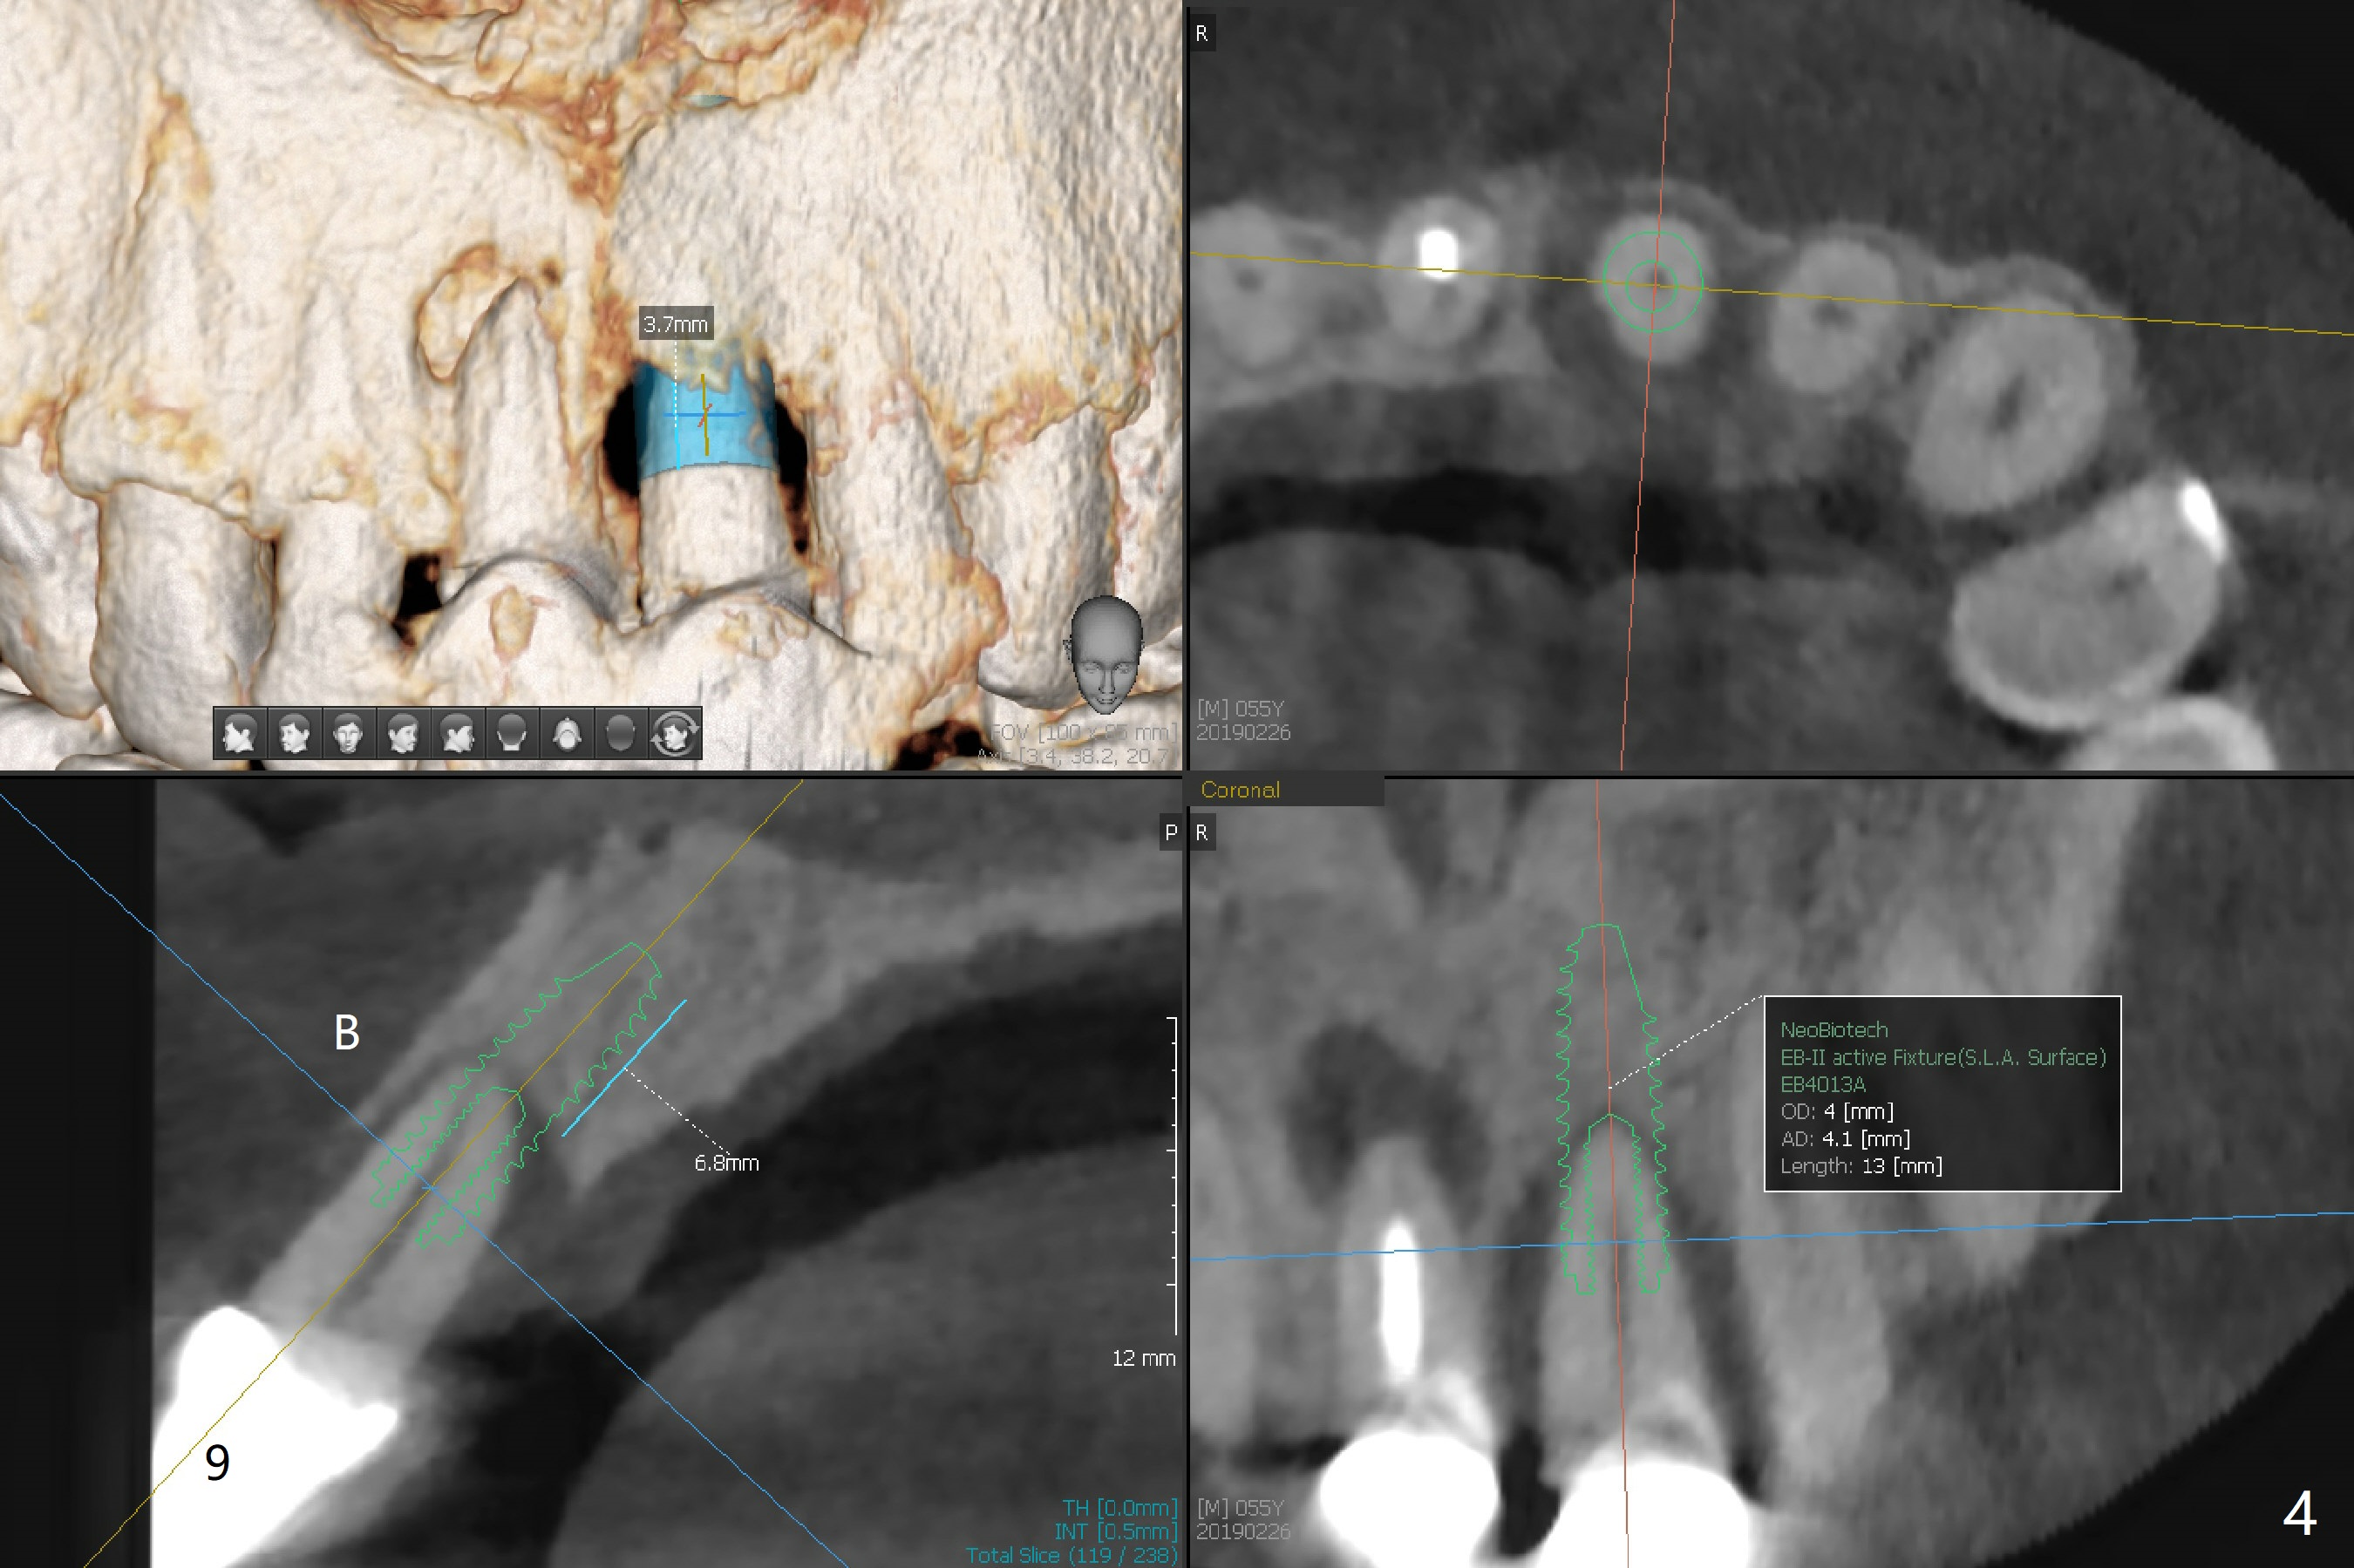

A 55-year-old man does not like the extruding tooth #9 (Fig.1,2). While there are fistulae associated with the two central incisors (arrowheads in Fig.1,2), bone loss appears to be apical at #8 and crestal at #9 (Fig.3 *). To avoid iatrogenic bone loss associated with two neighboring implants in the cosmetic zone, apicoectomy is to be performed at #8, while an immediate implant will be placed at #9 with guide at the same time (Fig.4). Furthermore there is missing or thin buccal plate at #8 (Fig.5 B).